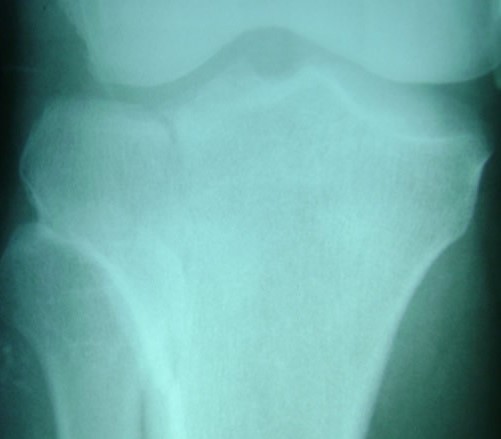

Tanatología-Necropsia